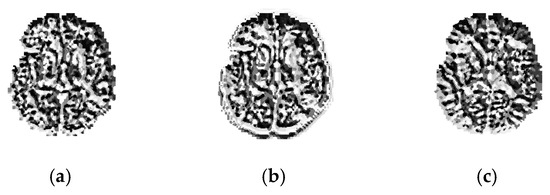

2.3. VGG-SegNet

2.4. Image Features